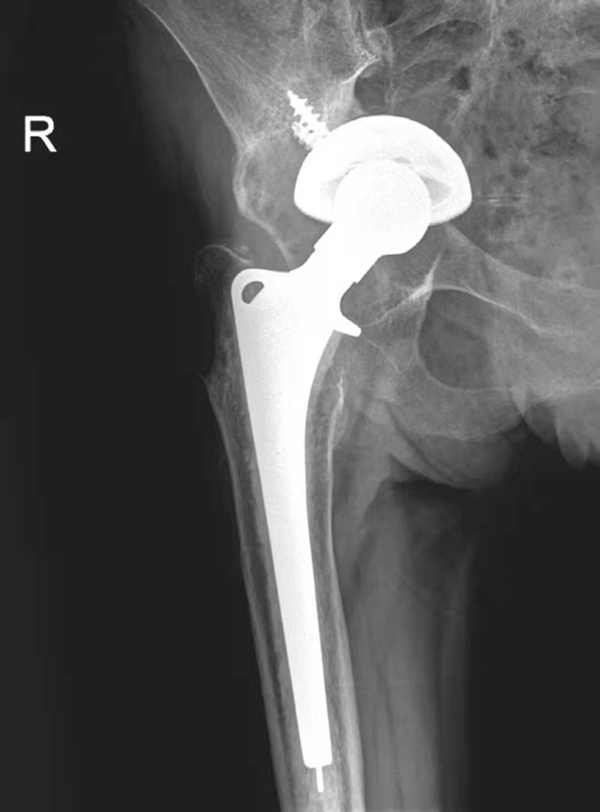

图4 右侧人工髋关节置换术后感染并松动

女性,89岁。发现右大腿中段后侧流脓2个月余。平片,示右股骨上段骨密度增高,内侧骨膜增生,假体周围骨质吸收,髋臼杯内陷,人工股骨柄部内移